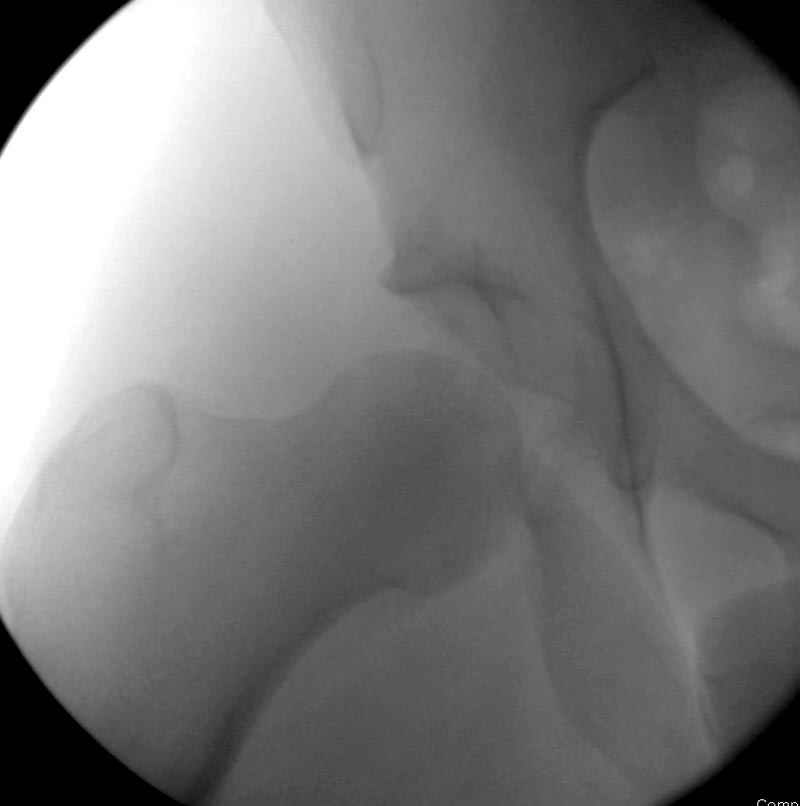

Со всеми рекомендациями согласен, и по этой схеме хотели продолжить наше обследование, но учитывая то, что вывих не смогли вправить, решение приняли - ургентно оперерировать.

5:24 Рентгенограмма таза, вызывают врача ортопеда (снимок N1), его диагноз: закрытый переломо-вывих правого тазабедренного сустава, получает добро на закрытую репозицию в приемном отделении

5:38 Дважды неудачная попытка закрытой репозиции в приемном отделении

6:20 ответстенный врач принимает решение о репозиции в условиях операционной, предупреждаются родственники и больной, что при неудачной закрытой репозиции, о возможности открытой репозиции и фиксации задней стенки вертлужной впадины.

7:30 начало операции, больной на спине, попытка репозиции после анестезии N3, укладка больного на боку, доступ Kocher- Langenbeck, состояние седалищнего нерва около 2.5см кровоподтек, через joistick головка бедра приподнята, освобовождение сустава, фрагмент заднего края более 3х4 см репонирован на свое место. После промывания

сустава, репозиция вывиха (N4), фиксация фрагмента 2.7(4) мм шурупами и допольнительно реконструктивной пластиной на 8 дырок, фиксация 3.5мм шурупами проксимально и дистально.

Интраоперционные N5 косая запирательная и N6 подвздошный снимок

11:50 больной в послеоперационной, рентгенограмма N7, компьютерная томограмма в тот же день N8-10